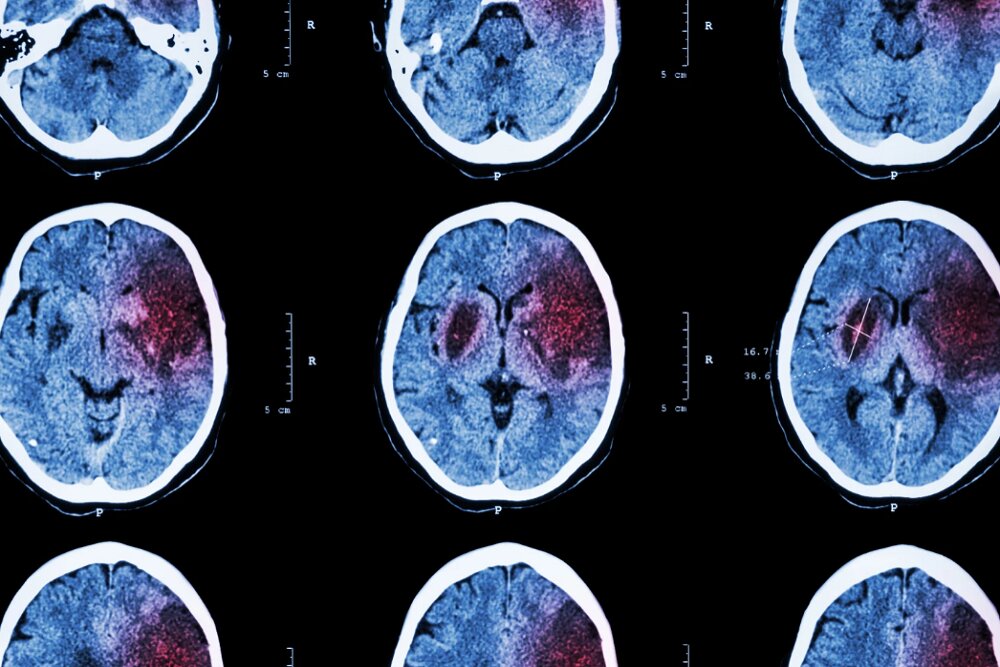

وضعیت بروز سکته مغزی در ایران

عضو هیاتعلمی دانشگاه علومپزشکی شهید بهشتی درباره نتایج مطالعات بروز سکتههای مغزی در ایران گفت: نتایج مطالعات میزان بروز سکته مغزی در ایران مشابه است؛ این در حالی است که اختلاف زمانی ۱۰ ساله دارند. نتایج مطالعات بروز سکته مغزی بیانگر این است که بروز سکته مغزی در ایران حدود ۱۵۰ به ازای هر ۱۰۰هزار نفر در هر سال است. البته میزان بروز سکته مغزی در کشور از متوسط جهانی بیشتر بوده و حدود ۱.۵ برابر متوسط جهانی است.